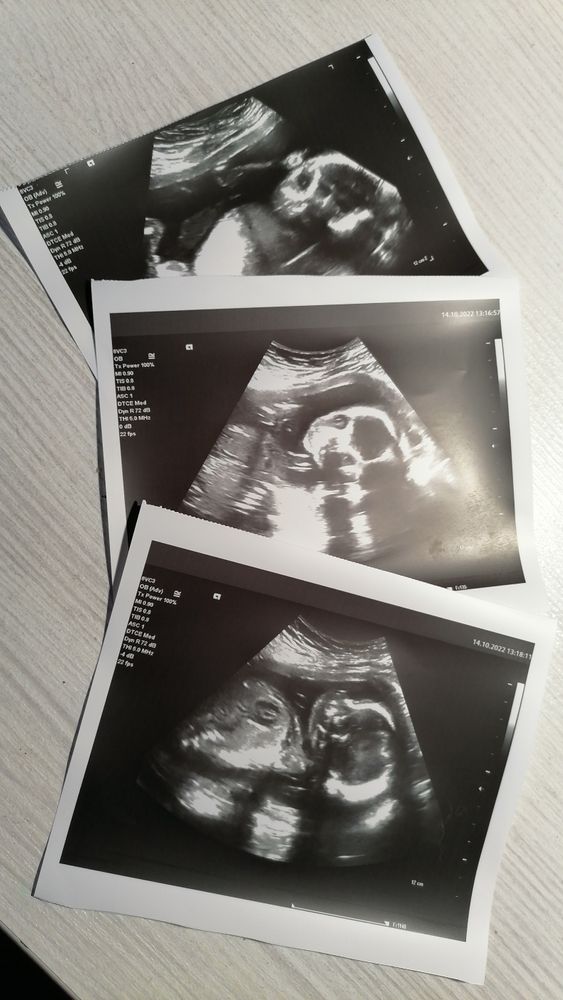

Сходила ещё раз на узи)

УЗИ, КТГ, доплерДевочки , привет) дело такое, ходила на 2 скрининг в 18+3, малыш обгонял на пару дней и весил 270 грамм, посоветовали ещё сходить на 20-21 неделе. Так вот сегодня 20+3, сходила ещё раз , в итоге малыш целых 415 грамм и по размерам соответствует на 21+2.. сказали , что все хорошо, якобы немного крупненький( но мол мальчик же) вот немного смутил вес , не большой ли? А то родится 5 кг, ничего хорошего 😰